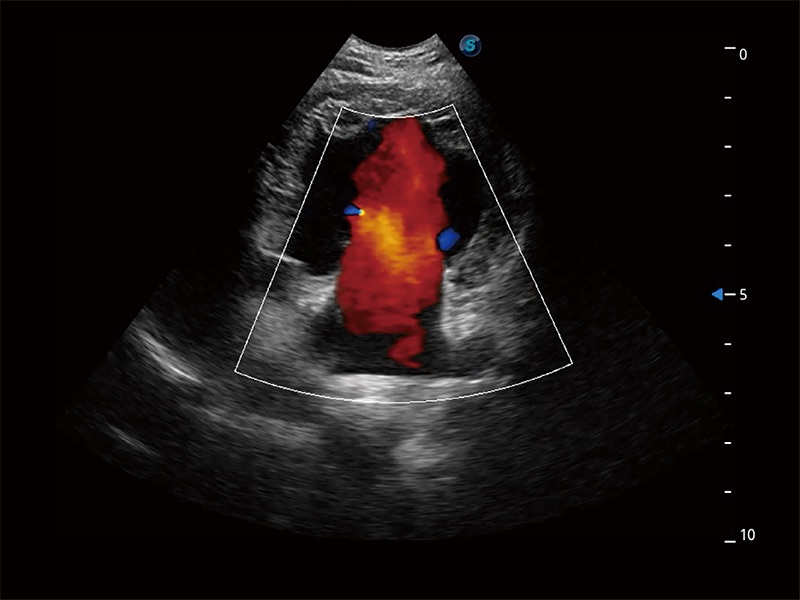

在傳統(tǒng)二維血流成像的基礎(chǔ)上,呈現(xiàn)血流的立體感,具有動(dòng)感的生命力之美。即便是微小的血管也能輕松應(yīng)對(duì),提高了血流的視覺(jué)敏感性。